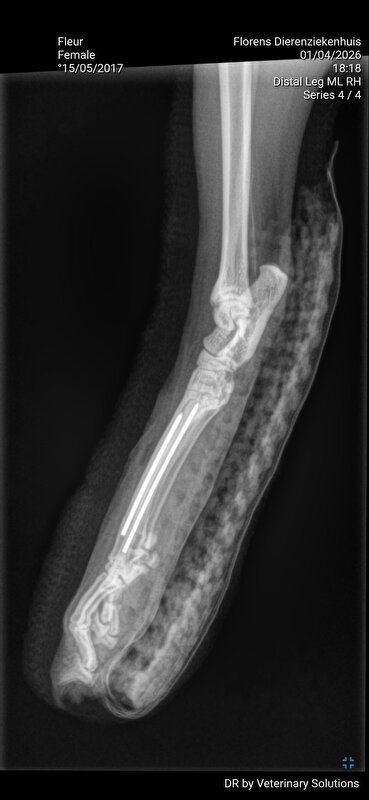

Dag 2: ik laat Fleur achter voor het maken van de foto's. Aan de assistente vertel ik dat Fleur zich goed gedraagt. Fleur is nml best een lief poesje. Er worden 3 foto's gemaakt en deze hoop ik nog te ontvangen om hier te kunnen plaatsen. 2 teentjes gebroken en 1 bot dusdanig naar buiten gekanteld dat deze bijna door steekt.

De assistente contact mij voor overleg: de operatie zou rond de 1700 euro uitkomen en er komen meermaals afspraken voor het spalken en de controle à 75 euro per keer.